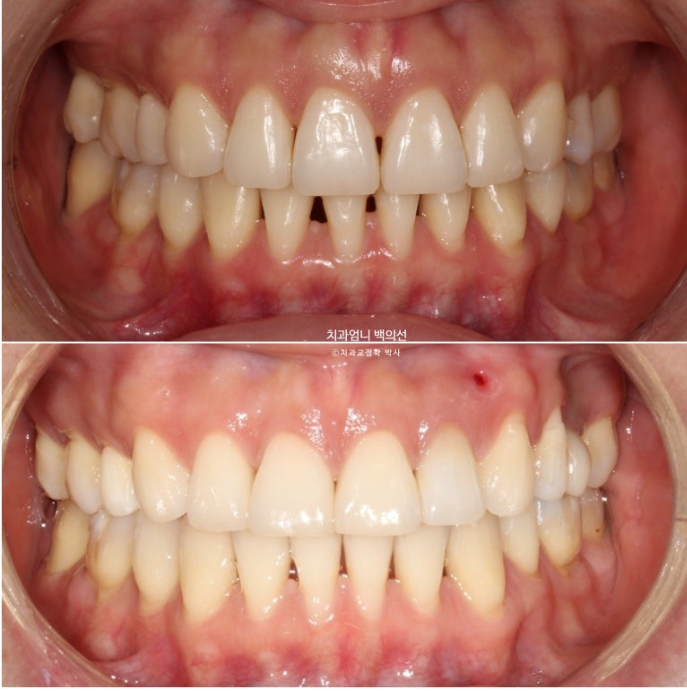

교합 안정화 및 마무리 과정을 거쳐 25년 6월, 드디어 재교정 치료를 마무리 했습니다.

25.06

총 치료기간은 1년 10개월 입니다.

이제 앞니 중심선은 코와 인중과 정확히 맞습니다.

2급이었던 양측 어금니 교합관계는 비로소 1급이 되었습니다.

23.08~25.06

옥니였던 위 앞니 각도의 개선이 뚜렷하며 뒤로 밀려있던 아래턱이 다시 나오면서 안모가 좋아졌습니다.

옥니였던 앞니가 역교정을 통해 정상으로 개선되어 다물었을 때 뒤로 밀렸던 아래턱이 이제 편하게 물립니다.

아래턱이 뒤로 밀리는 바람에 무턱처럼 보였던 부분도 개선이 되었습니다.